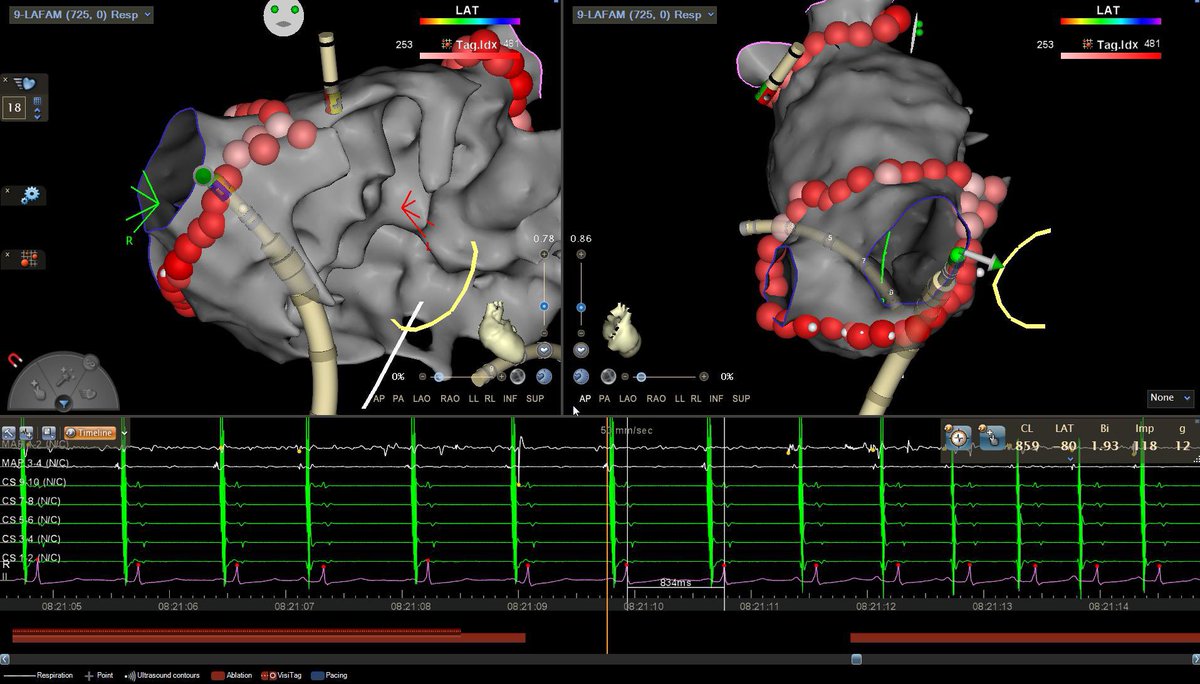

Is #PulseFieldAblation replacing RF Ablation?

Dr. Kristopher Heinzman & @pkothapalliMD explore its clinical promise, training risks & how EPs decide which patients fit PFA vs RFA.